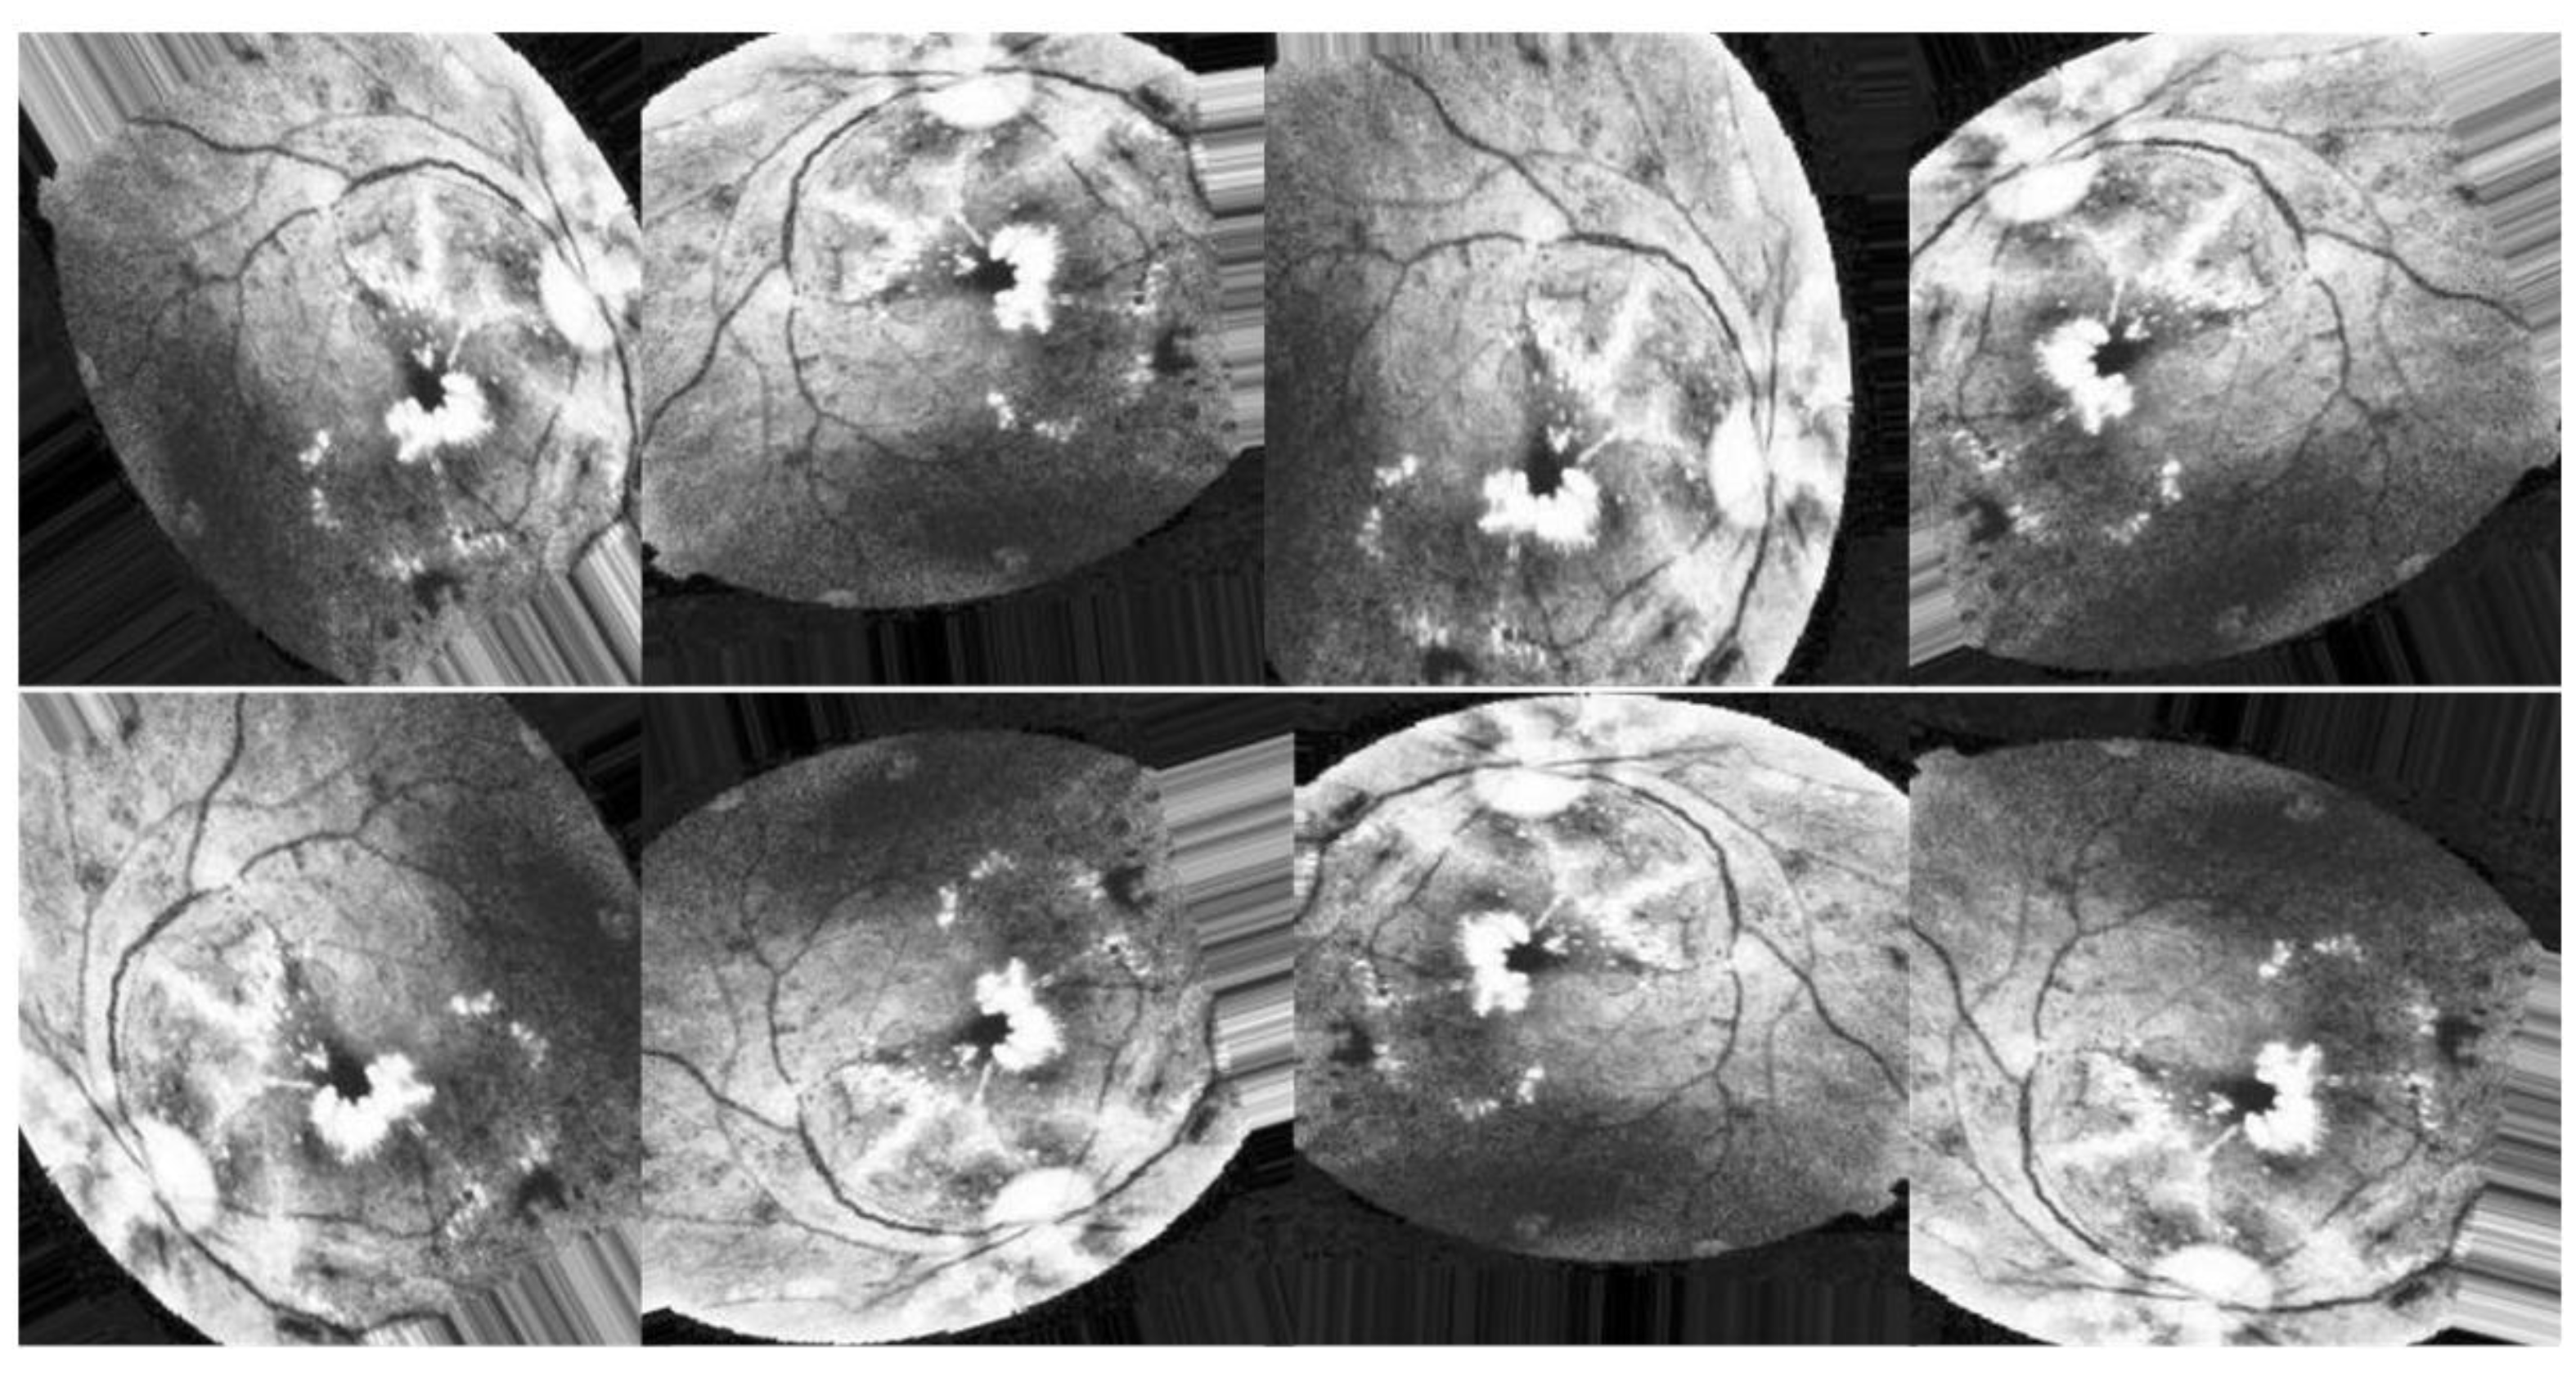

All previous edits to images in the training set are applied to generate new samples for the network. While the total number of images is the same in all scenarios, Figure 8, Figure 9 and Figure 10 illustrate the purpose of data augmentation, which is to increase the quantity of data by providing slightly altered copies of the existing data or newly synthesized data derived from the existing data using the same parameters in all three scenarios. Here are the three scenarios that were used to train DenseNet-121:

The second scenario is to apply augmentation techniques to the enhanced images utilizing CLAHE, HIST, and ESRGAN, respectively, as depicted in Figure 9.

Figure 9. Examples of augmenting the same image with different methods (CLAHE + HIST + ESRGAN).